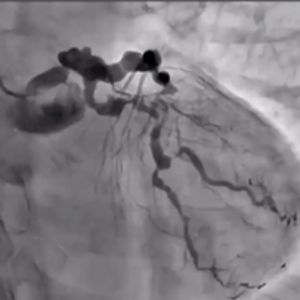

Join us for a live-streamed workshop where the world's top cardiologists gather to explore cutting-edge techniques in PCI (Percutaneous Coronary Intervention), with a special focus on the advanced Tip Detection Antegrade Dissection Re-entry (TD-ADR) method.

Innovative Techniques: Master the latest technologies, including the highly-regarded 3D wiring technique and TD-ADR, developed in Japan, and stay at the forefront of medical innovation.